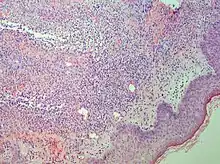

Interface dermatitis with vacuolar change

| Generally/Not otherwise specified | Typical findings, called "vacuolar interface dermatitis":[6]

|

An interface dermatitis with vacuolar alteration, not otherwise specified, may be caused by viral exanthems, phototoxic dermatitis, acute radiation dermatitis, erythema dyschromicum perstans, lupus erythematosus and dermatomyositis.[2]